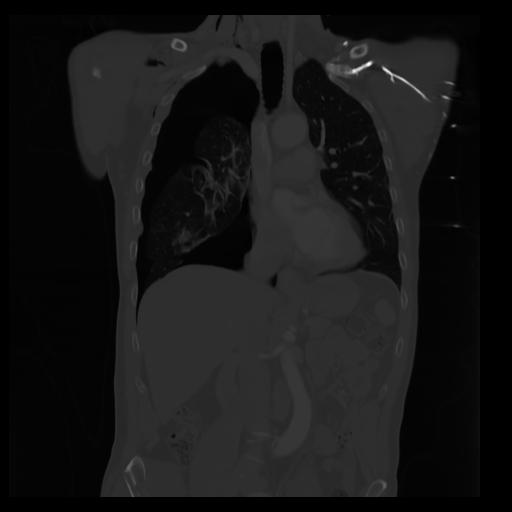

29 CUERPO,CE,Coronal,3.000,CUERPO,Coronal,